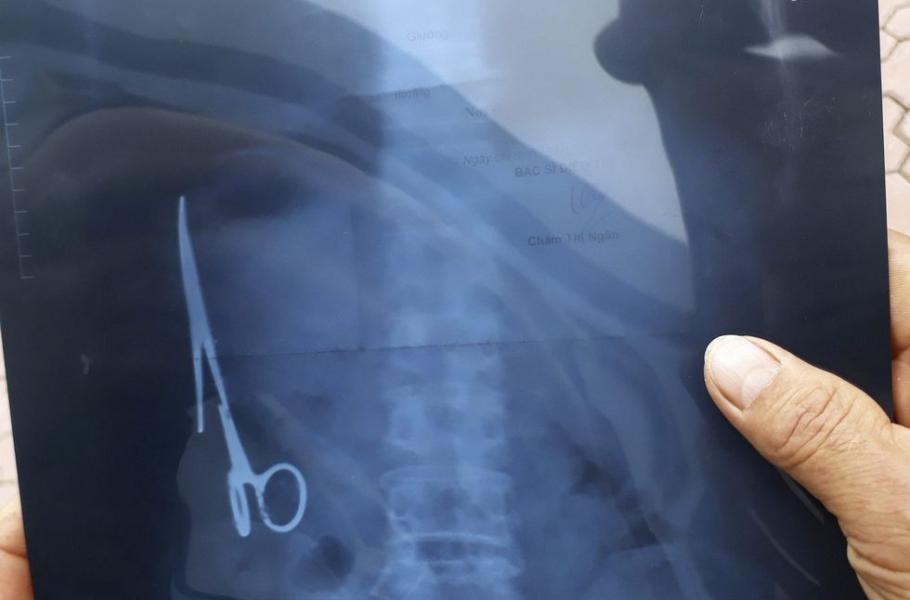

Praktický lékař původně přisuzoval občasné bolesti břicha 54letého Ma Van Nhata žaludečním vředům, když na ně ovšem neúčinkovala běžná léčba, poslal muže na rentgen. Vyšetření pak v levé části pacientova podbřišku překvapivě ukázalo 15cm chirurgické nůžky.

Podle lékařů, kteří je následně operativně vyjmuli, již zrezivělý nástroj přirůstal k orgánům a Van Nhat ho zřejmě v útrobách nosil velmi dlouho. Muž domněnku potvrdil: Poslední operaci, při které mohl k nečekanému „pokladu“ přijít, podstoupil v roce 1998, a s nůžkami v břiše tak žil minimálně 18 let.